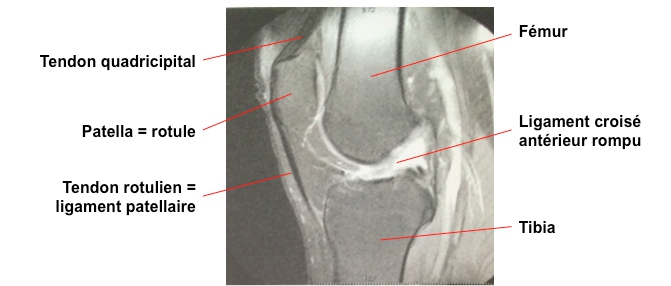

Rupture Du Ligament Croise Anterieur

Rupture Du Ligament Croise Anterieur Du Genou Ligamentoplastie Du Genou